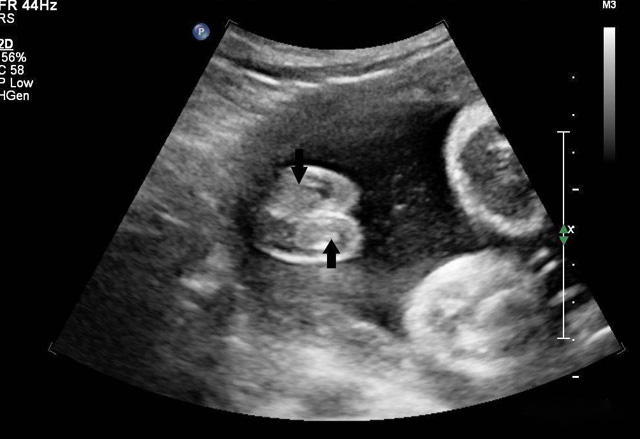

三維超聲技術可用于心臟、腹腔、婦科、產科、小器官、血栓、血管成像等多方面。